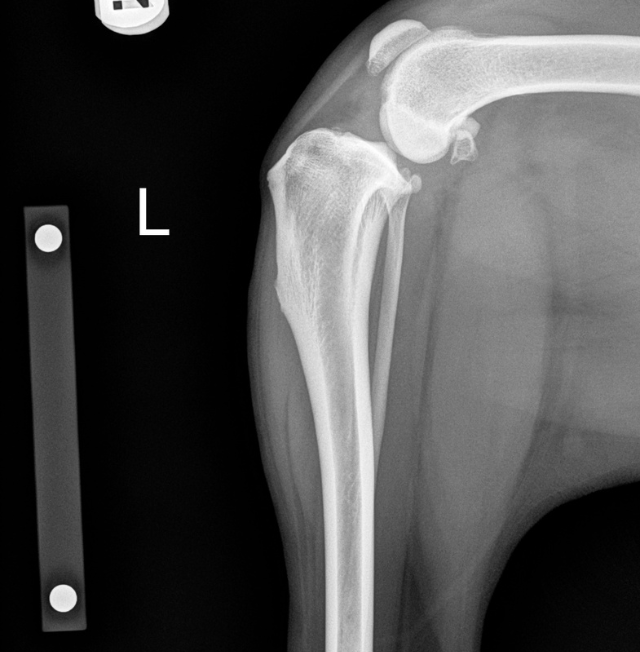

Tibial Plateau Leveling Osteotomy (TPLO) in Rome, GA

At Animal Medical Center of Rome, we offer TPLO surgery to treat cranial cruciate ligament (CCL) injuries in dogs, a common cause of hind limb lameness. This advanced orthopedic procedure stabilizes the knee joint, reduces pain, and allows pets to regain mobility more effectively than conservative treatments alone.